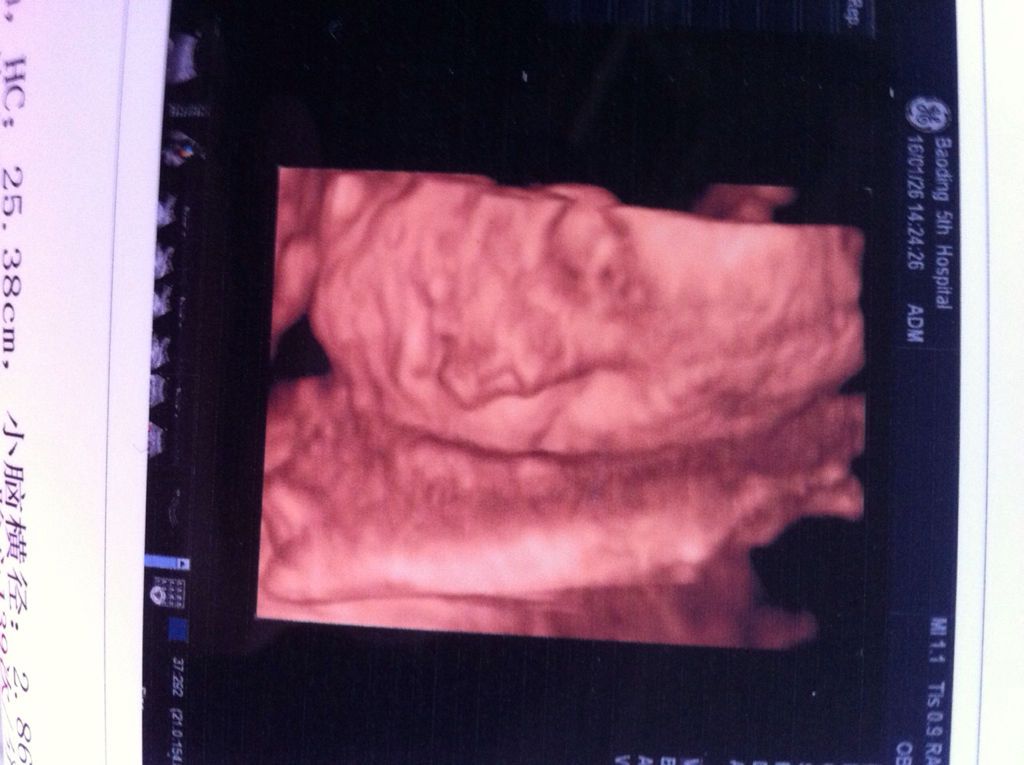

专家帮我看看,这个四维彩超是不是兔唇啊 点击展开 匿名用户 2016-01-31 22:10 满意回答 你好,因为四维属于是动态观察的,方便医生观察概脚胎儿在子宫腔内的情况,所以拍照可能是会有一些奇怪的挤乔,这貌清眨个不需要担心,如果孩子真的有问题,那超声提示上面是会说明的,没有讲的话你可以不需要担心 ˿5784 2016-01-31 22:11 宝宝知道提示您:回答为网友贡献,仅供参考。 相关问题 四维彩超可以看出胎儿兔唇吗? 大家帮我看看吧,最后一张不会是兔唇吧?好担心啊! 请帮我看看,现在6个月了查出兔唇严重,现在怎么办?